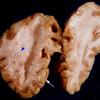

SSPE (2)